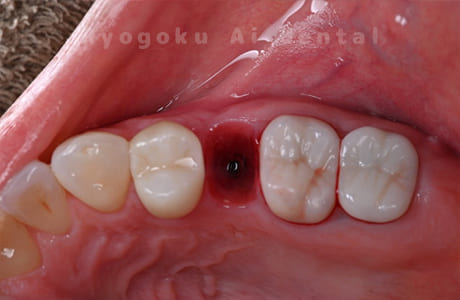

Case07

-

- 原因

- 右下6番歯根破折

- 治療内容

- インプラント治療

- 治療費用

- 約600,000円

右下の腫れが治らないとの事でご来院された患者様です。歯が割れていたため、抜歯を行い、骨に代わるお薬を入れ、インプラントを埋入致しました。経過良好で大変満足していただけました。

<リスク・副作用>

治療後、痛みや違和感、出血、腫れなどが出る事があります。喫煙者、糖尿病などの方の場合、歯が生着しない場合があります。